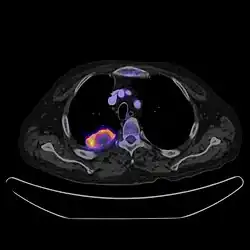

Positron emission tomography–computed tomography is a hybrid CT modality which combines, in a single gantry, a positron emission tomography (PET) scanner and an x-ray computed tomography scanner, to acquire sequential images from both devices in the same session, which are combined into a single superposed (co-registered) image. Thus, functional imaging obtained by PET, which depicts the spatial distribution of metabolic or biochemical activity in the body can be more precisely aligned or correlated with anatomic imaging obtained by CT scanning.[41] PET-CT gives both anatomical and functional details of an organ under examination and is helpful in detecting different type of cancers.[42][43] Hybrid PET-CT systems have become more effective with the integration of anatomical details from CT scans. This integration allows for the creation of an attenuation correction map, which helps refine PET images. These advancements have notably reduced examination duration, increased diagnostic accuracy, and instilled greater confidence in the accuracy of diagnoses.[44][45] In oncology, studies show that using PET-CT together is better for accurately staging and restaging than using CT or PET alone.[46][47][48]